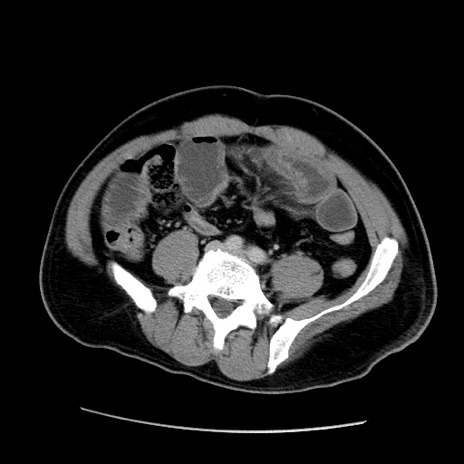

冠状断像

【症例】50歳代男性

【主訴】腹痛

【現病歴】AVMからの被殻出血のため回復期リハ病棟入院中。 本日午後3時頃急に下腹部痛が出現した。

【既往歴】AVM、被殻出血、虫垂炎、高血圧

【身体所見】意識晴明、左半身不全麻痺、会話の理解は良好、36.5°C、腹部:膨隆、全体に板状硬、下腹部正中に圧痛点あり、反跳痛-、筋性防御不明、右下腹部にope scar

【データ】WBC 9400、CRP 0.06